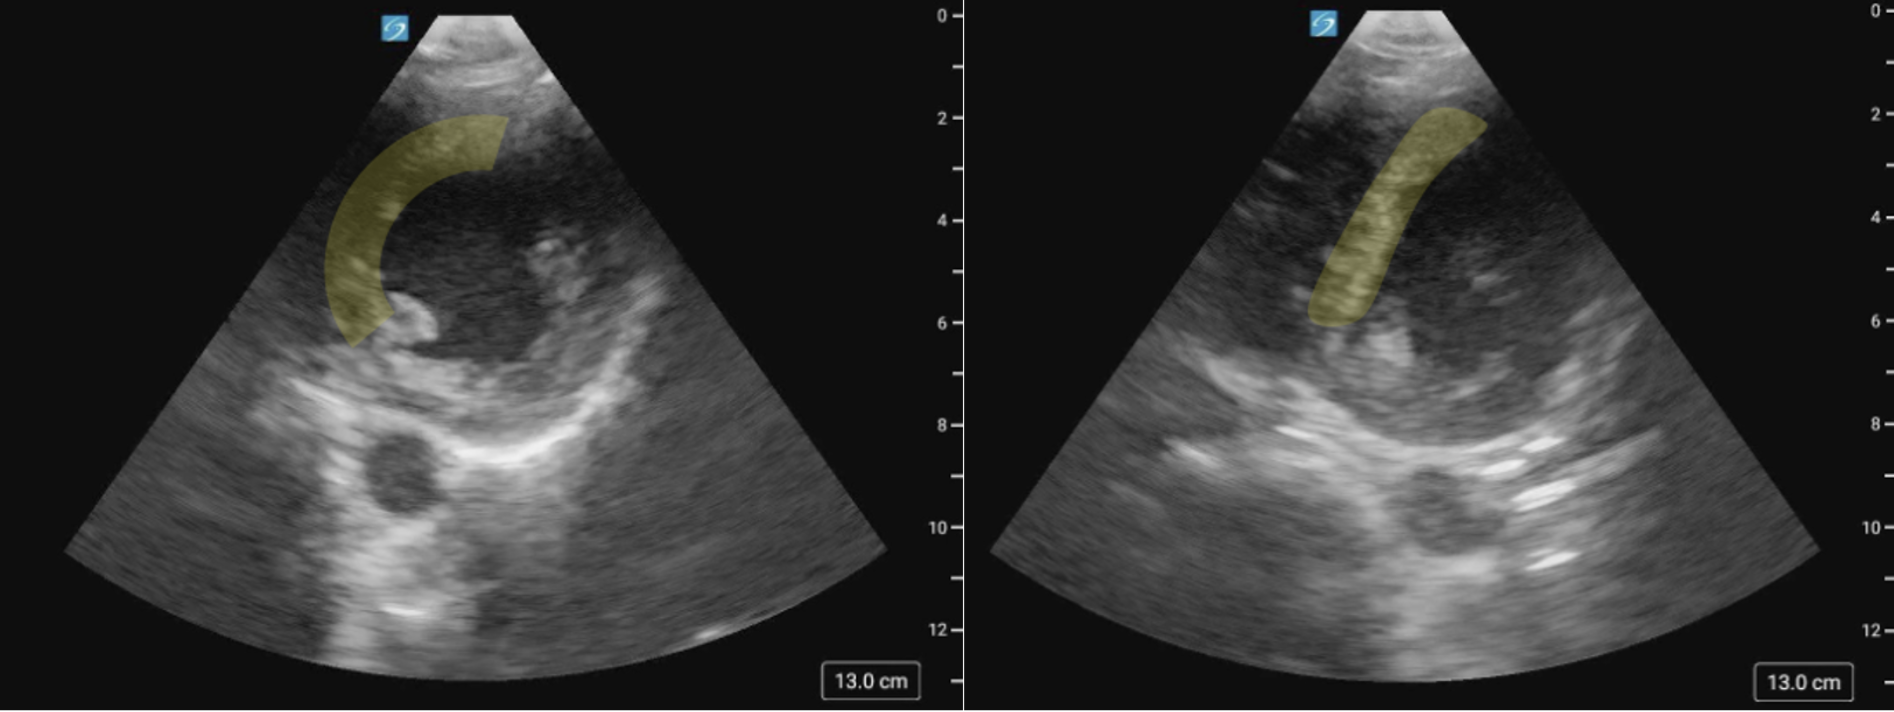

Similar to LV function assessment, RV strain imaging is susceptible to foreshortening and off-axis imaging. In the PSAX window, a low imaging window or off-axis rotation can produce apparent septal flattening (“pseudoflattening”) (figure 24, 25), which may mimic RVVO and/or RVPO and lead to inappropriate conclusions or interventions [17, 24,25]. In the A4C view, foreshortening may occur when imaging from too high of an intercostal space, making the RV appear truncated or blunted (figure 26,27). Always confirm you are at the appropriate intercostal space by scanning through adjacent levels in each window.

Figure 24 (a) PSAX image of the IVS on axis versus (b) Pseudoflattening of the IVS in the same patient, secondary to a low scanning window.

Figure 25 (a) PSAX view of the IVS on axis versus (b) Pseudoflattening of the IVS in the same patient, secondary to a low scanning window.